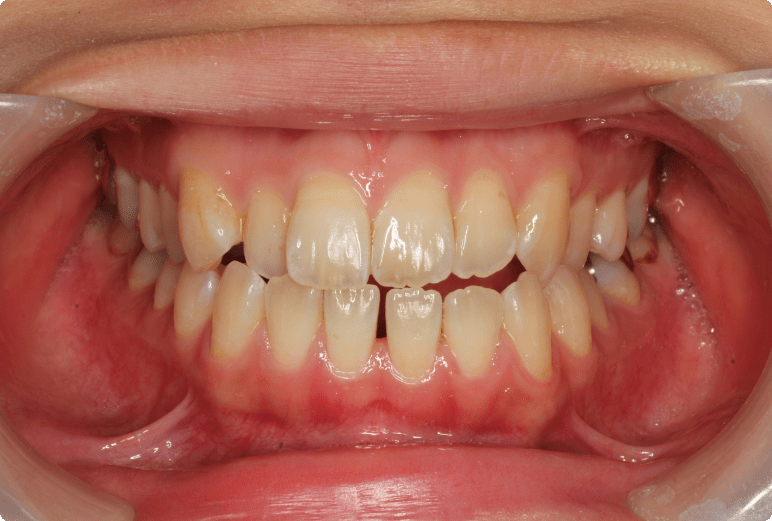

八重歯を改善した症例

BEFORE

AFTER

症例概要

年代、性別

12歳 女の子(成人と同様の矯正治療)

主訴

八重歯

診断

骨格性Ⅰ級、歯性Ⅱ級、前歯部叢生

治療内容

上顎左右4番抜歯、唇側ワイヤー矯正、リテーナー

治療期間

2年+メンテナンス

治療リスク

痛み、歯根吸収、歯肉退縮

治療費用

990,000円(税込)